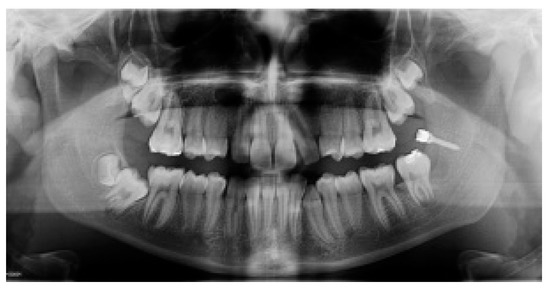

The site and angle of insertion, the length and the diameter of titanium miniscrew (BENEfit, psm, Tuttlingen, Germany) were determined in the planning phase on a panoramic radiograph (length 13 mm; 2.3 mm diameter) and clinically confirmed during the surgery. After the self-drilling miniscrew insertion, two metal brackets were bonded on the buccal and oral surfaces of MM2 crown. At the end of surgery an elastic chain was secured to the miniscrew head and connected to the metal brackets bonded on buccal and oral surfaces of MM2 crown (Figure 2A,B); a close/submerged traction was performed. On the head of the miniscrew was screwed an abutment with two brackets (Figure 2A,B); an elastic chain was applied to each bracket (Figure 2B). Each elastic chain was activated between the bonded button on the surface of the second molar to the bracket of the miniscrew. A short elastic chain was used that was stretched approximately twice. Finally, the surgical site was sutured (Figure 2C).

Figure 2.

(A,B) View of inserted self-drilling miniscrew in the retromolar area, the buccal and oral metal brackets on the crown of mandibular second molar (MM2) and the orthodontic traction with the elastomeric chain; (C) Surgical incision closure with sutures.